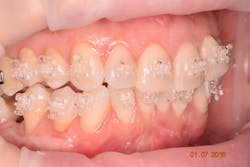

Because of her high-stress job and infrequent use of her night-guard, clenching and bruxism habits were reflected in her dentition. In addition to malocclusion and crowding, her upper right canine has a lingual enamel chip with an incipient crack line (figures 2a and 2b).

- Orthodontic correction to improve crowding, occlusion, spacing, and upright No. 31 for future restorative and implant dentistry

The patient demonstrated excellent healing one month post-operatively (figure 8) with a significant increase in keratinized tissue. This increase in soft tissue will aid in the prevention of further recession during orthodontic therapy (figure 9) as well as assist in the coronal advancement of tissue post orthodontic therapy for the purposes of root coverage. Most importantly, the patient was extremely happy with the result.